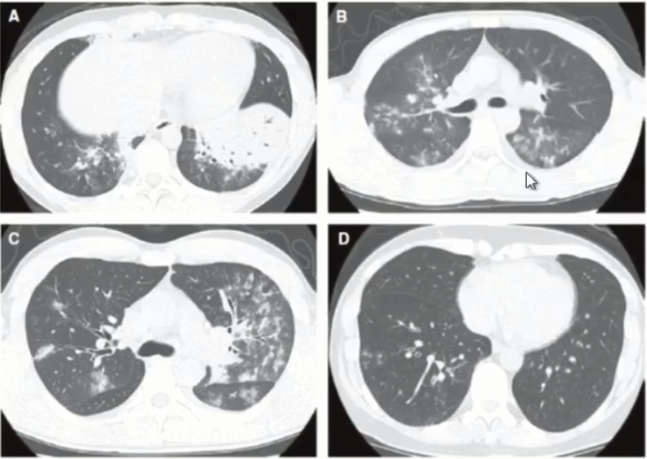

诊断篇:肺炎支原体肺炎的影像学诊断

肺炎支原体肺炎时ct怎么看

成人支原体肺炎的ct表现

一眼就认出你是支原体肺炎而不是肺结核